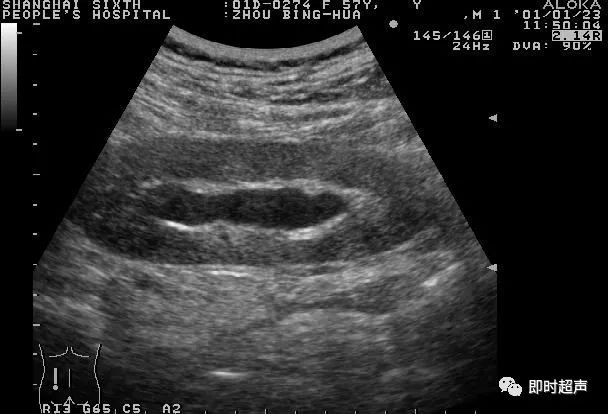

正常肾二维声像图有周边的肾轮廓线和肾中央的肾窦回声,二者均为高回声。二者之间的肾实质呈低回声,肾锥体回声较肾皮质回声更低。肾窦内可以见到条状低回声为肾静脉回声(图4-1-1)。膀胱充盈时或大量饮水后,肾盂回声常有轻度分离,但排尿后肾盂分离可减少,正常肾在呼吸时能随呼吸活动。

图4-1-1 正常肾声像图